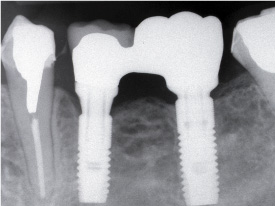

左上顎に新しい骨を作って(上顎洞底挙上術)インプラントを入れました。

骨のない部分に骨を新しく作ることができます。

歯を抜いて同時にインプラントを入れました。